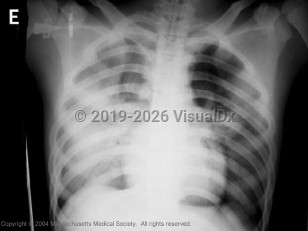

Aspiration pneumonia